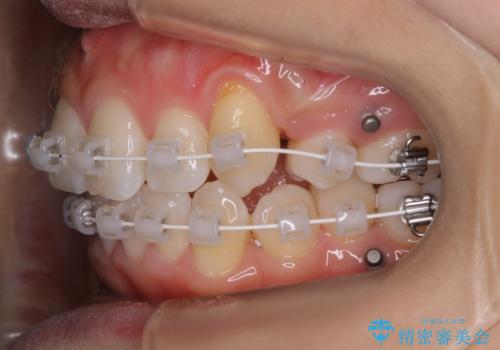

ワイヤー矯正 抜歯本数を最小限にし、八重歯のない歯並びに

- 上顎の八重歯が気になるとのことで来院されました。

左側のかみ合わせは、歯1本分かみ合わせが前にずれていました。上顎左右の奥歯を2本抜歯しています。

下顎は、歯の側面を少し削ることで歯並びを整えました。

上顎と下顎の奥歯の抜歯(計4本)を行う治療方法もありますが、口元のバランスのことも考え、上顎の抜歯のみで、治療を行いました。

八重歯でがたつきは重度でしたが、きれいな歯並びにすることができました。

がたつきだけでなく、奥歯の噛み合わせのずれの調整もしっかり行いました。

奥歯のずれの調整は時間がかかりますが、矯正後の歯並びの安定度が向上します。